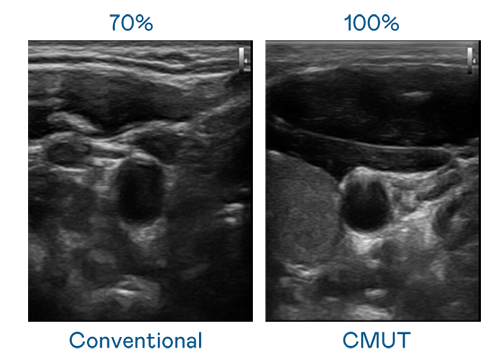

CMUT 技術是一種用電容式微機電元件來產生超音波訊號的技術。與傳統 PZT 壓電式技術相比,CMUT 頻寬增加 30%,更寬頻的超音波訊號讓影像解析度大幅提升,是實現高影像品質醫療超音波掃描、促進精準醫療發展的關鍵技術。

超音波影像的解析度高低,首先取決於探頭能發出的訊號頻寬。人生就是搏尊龙 CMUT 可提供高清晰的超音波訊號,提供高頻寬、高靈敏度、影像紋理細節更高的超音波影像,協助醫護人員縮短影像判讀時間及利用精準的醫療影像進行診斷。